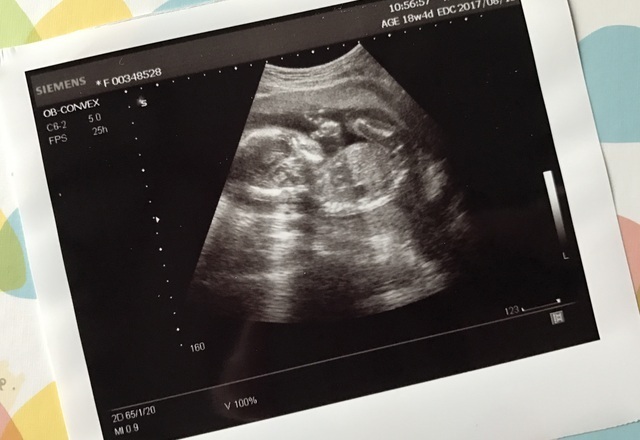

18週0日(18w0d・女の子)|surfrie さん(38歳)

エコー写真撮影時のエピソード:

なぜか、毎回健診の時のエコー当てますゆの時、いつも顔辺りに手を当てて、いないないばぁ〜のいないいないのポーズだった。すごく可愛かったけど結局、顔を1度もエコーでは見れないまま出産まで行った。足もバタバタさせていたので

男女どちらかもいまいちはっきり分からずで出産まで行った。